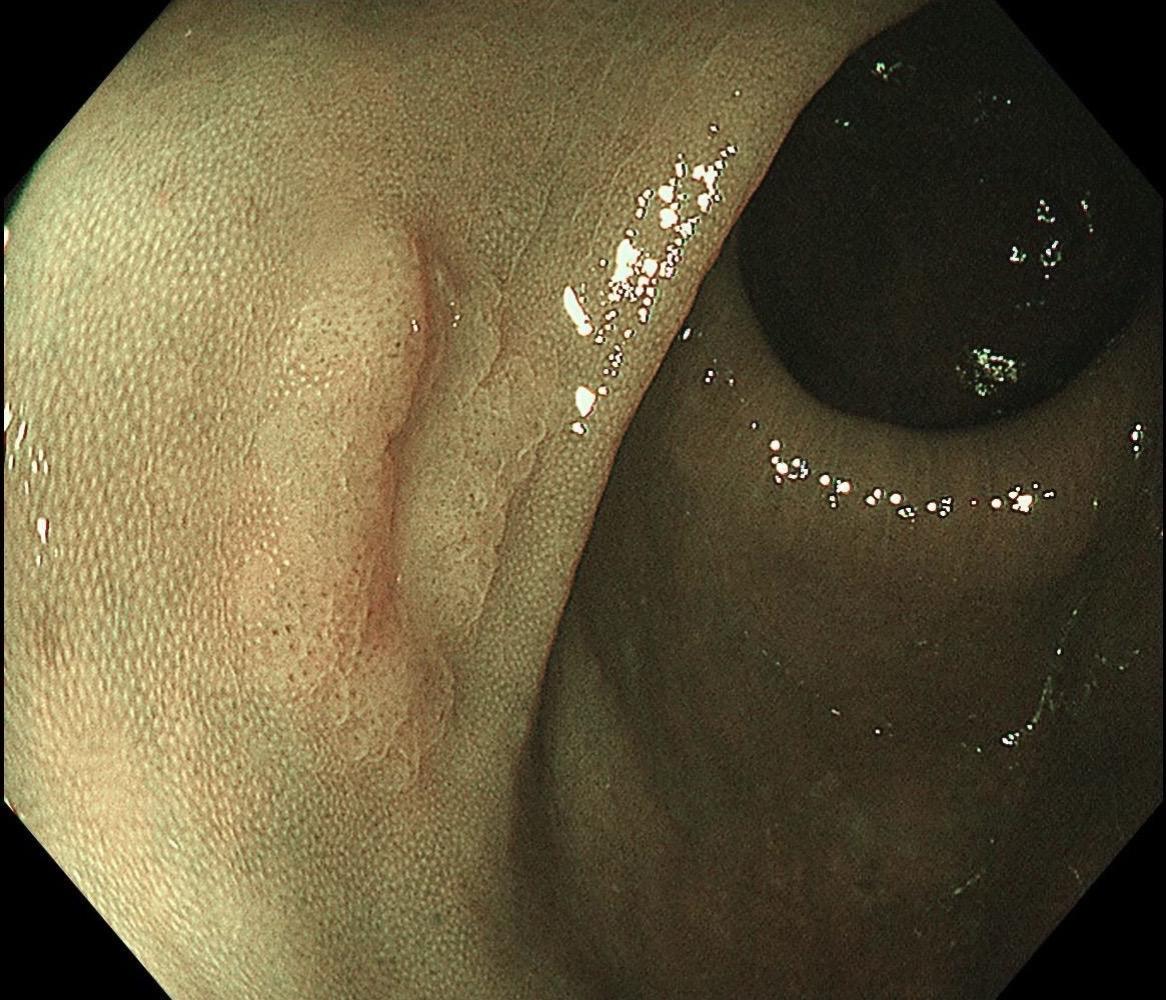

结肠SSL 醋酸染色。染色效果不亚于靛胭脂,结合NBI,Near focus观察表面结构非常OK,下次让护士长买大桶装的,1桶6块9,可以喷一年,哈哈……

结肠SSL 醋酸染色。染色效果不亚于靛胭脂,结合NBI,Near fo...